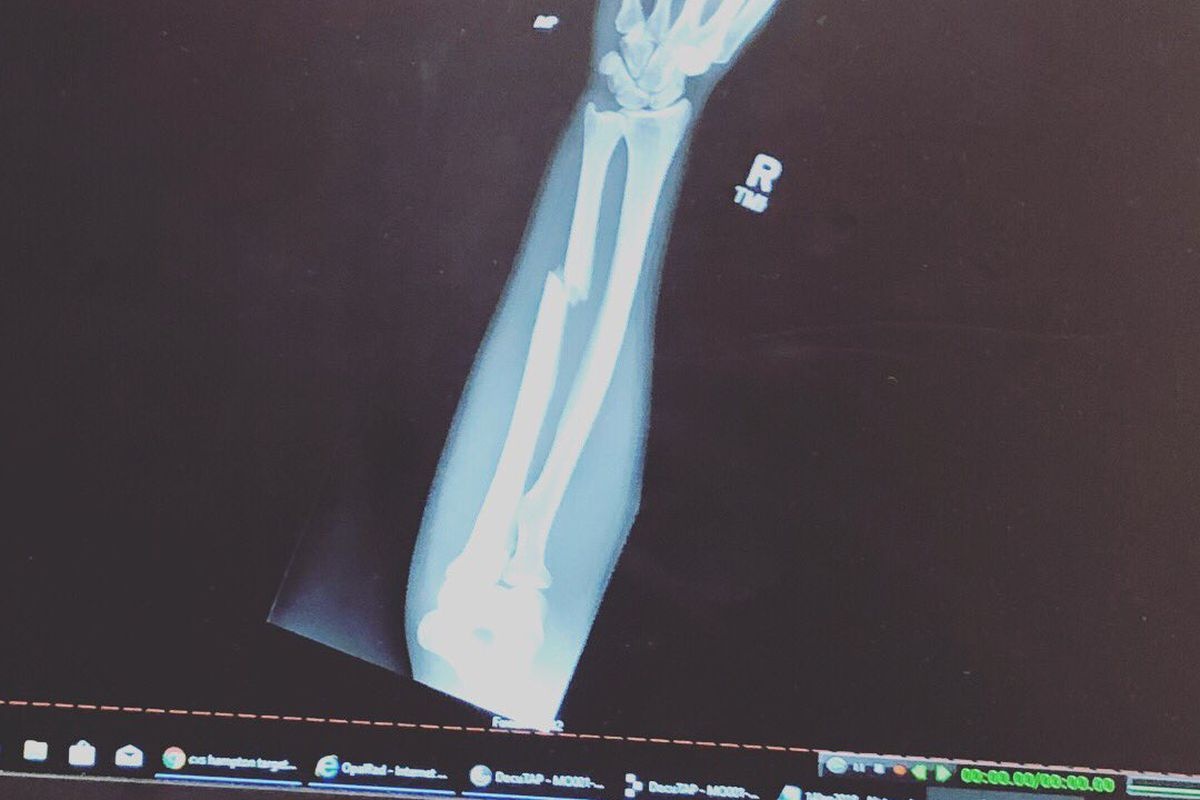

VanZant lấy lại thế trận sau đó. Tuy nhiên, trong một nỗ lực tung đòn đấm xoay, tay phải của cô không may bị gãy.

Chia sẻ về chấn thương, VanZant cho biết: "Tôi bị gãy tay ở hiệp đầu tiên. Tôi có thể xin thua nhưng đã tiếp tục chiến đấu và vẫn tung ra những cú phải tay".

VanZant ra đòn bất chấp vết gãy ở tay phải.